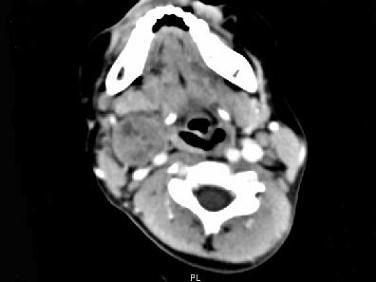

问题 女,4岁,右侧颈部可扪及一包块约两个月,无热无痛,CT如图所示,最可能的诊断为 ( )

选项 A、咽旁神经纤维瘤 B、咽旁小唾液腺混合瘤 C、咽旁副神经节瘤 D、咽旁脓肿 E、咽旁血管外皮瘤

答案 A